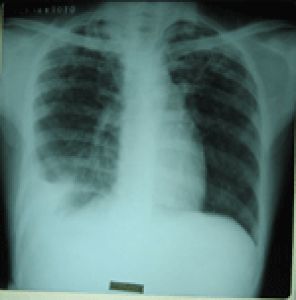

2.X線檢查胸腔積液在300ml以下時,後前位X線胸片可能無陽性發現。少量積液時肋膈角變鈍,積液量多在500ml以上,仰臥位透視觀察,由於積聚於胸腔下部的液體散開,復見銳利的肋膈角。也可患側臥位攝片,可見肺外側密度增高的條狀影。中等量積液表現為胸腔下部均勻的密度增高陰影,膈影被遮蓋,積液呈上緣外側高,內側低的弧形陰影。大量胸腔積液時,肺野大部呈均勻濃密陰影,膈影被遮蓋,縱隔向健側移位。滲出性胸膜炎胸腔積液有些可表現為特殊類型,常見的有:

病毒分子(2)滲出性胸膜炎:滲出性胸膜炎的症狀比干性胸膜炎明顯。患者先有乏力、畏寒、虛汗、全身不適、逐漸發熱、胸痛、咳嗽、深呼氣或活動時加劇,隨著滲液的逐漸增加,肺臟受壓,則胸悶、氣短更為顯著,大量滲液阻礙了壁層和髒層胸膜之間的摩擦,疼痛反而減輕,由劇痛變為純痛、脹痛或逐漸消失。大量的胸腔體積液可將氣管等器官推向健側並使肋間隙飽滿,心尖搏動移位或消失,膈肌下降。叩診時,積液上部呈濁音,下部呈實音。聽診時可有呼吸音減弱或消失,語顫減弱,積液上方肺臟受壓、氣量減少、可聞及支氣管呼吸潼。X線可發現積液的明確部位。